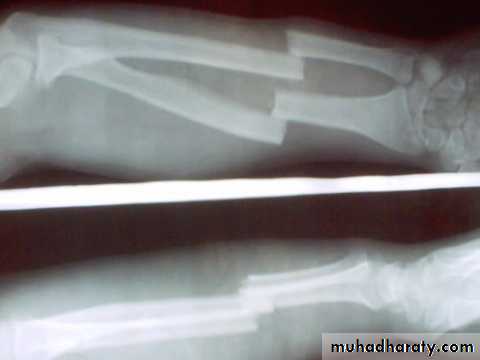

upper limb .Spiral fracture

3 weeks united * 2 consolidation.

Lower limb * 2.

Transverse fracture * 2 again.

In children the time shorter, in elderly longer